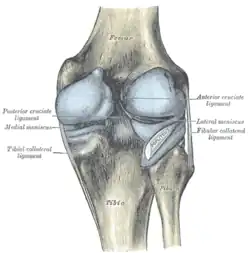

Menisken

Da die miteinander in Verbindung stehenden (artikulierenden) Gelenkflächen nicht genau aufeinander passen, wird diese „Ungleichheit“ (Inkongruenz) durch halbmondförmige Faserknorpelscheiben, die Menisken ausgeglichen, die den Drehbewegungen folgen können. Eine weitere Aufgabe der Menisken besteht in der Vergrößerung der Kontaktfläche zwischen Schienbein und Oberschenkelknochen.

Man unterscheidet einen Innenmeniskus (Meniscus medialis), der C-förmig, größer und etwas unbeweglicher (da mit dem Innenband verwachsen) ist, und einen Außenmeniskus (Meniscus lateralis), der kreisförmig, kleiner und beweglicher ist (da er mit keinem Seitenband verwachsen ist). Die Menisken sind im Querschnitt keilförmig. Die hohe Kante liegt außen, die niedrige innen. Da die Oberschenkelknochen genau in der Mitte direkt auf dem Schienbeinplateau und peripher auf den Menisken aufliegen, tragen diese einen wesentlichen Teil der Last.

Seitliche Bandsicherung

Das Knie hat zwei Seitenbänder: ein inneres (Ligamentum collaterale tibiale) und ein äußeres (Ligamentum collaterale fibulare). In Streckstellung sind beide Seitenbänder (auch Kollateralbänder genannt) gespannt und verhindern somit die Drehbewegung, in Beugestellung verkleinert sich der Krümmungsradius, Ursprung und Ansatz nähern sich einander an und die Bänder sind infolgedessen entspannt. Beide Seitenbänder stabilisieren das Kniegelenk in seitlicher Richtung (Frontalebene), damit ein Wegknicken in eine O-Bein-Stellung (Genu varum) oder X-Bein-Stellung (Genu valgum) verhindert wird.

Das Innenband (Ligamentum collaterale tibiale bzw. mediale) ist ein dreieckiges, flaches Band, das breitflächig vom Aufsatz des inneren Oberschenkelknochens (Epicondylus medialis femoris) zur Innenseite des Schienbeines (Facies medialis tibiae) verläuft. Es ist in die äußere Schicht der Gelenkkapsel eingebaut und mit dem Innenmeniskus verwachsen.

Das Außenband (Ligamentum collaterale fibulare bzw. laterale) ist ein kräftiges Band, das in seinem dorsalen Abschnitt zylinderförmig vom Aufsatz des seitlichen Oberschenkelknochens (Epicondylus lateralis femoris) zum Wadenbeinkopf (Caput fibulae) zieht. Es hat keine feste Verbindung zur Gelenkkapsel und den Menisken.

Zentrale Bandsicherung

Die Kreuzbänder (Ligamenta cruciata) ziehen von der Grube zwischen den Oberschenkelknorren zum Schienbein. Von der Seite und von vorn betrachtet überkreuzen sie sich dabei in ihrem Verlauf.

Vorderes Kreuzband

Das vordere Kreuzband (Ligamentum cruciatum anterius – bei Tieren Ligamentum cruciatum craniale) zieht von der vorderen Einmuldung zwischen den Schienbeinknorren zur Seite und etwas nach hinten, um an der Innenseite des seitlichen Oberschenkelknochens anzusetzen. Dabei teilt es sich in ein vorne-mittiges und in ein hinten-seitliches Bündel auf. Durch die weite Fächerung der Ursprungsfläche dieser Bündel ist sowohl bei Beugung, als auch bei Streckung ein Teil des vorderen Kreuzbandes gespannt. Dadurch verhindert es bei ausgestrecktem Bein eine Überstreckung (Hyperextension), während es bei Beugung dem Vorschub des Schienbeines entgegenwirkt („vordere Schublade“).

Hinteres Kreuzband

Das hintere Kreuzband (Ligamentum cruciatum posterius – bei Tieren Ligamentum cruciatum caudale) ist kräftiger und hat seinen Ursprung in der hinteren Einmuldung des Schienbeinplateaus und zieht nach vorne-mittig, um an der seitlichen Vorderfläche des inneren Oberschenkelknochens anzusetzen. Es spannt sich bei Beugung und verhindert damit ein nach hinten gerichtetes Weggleiten des Schienbeines (hintere Schublade). Bei ausgestrecktem Bein unterstützt das hintere Kreuzband das vordere beim Vorbeugen einer Überstreckung. Seine Hauptaufgabe ist jedoch die Stabilisierung des Knies bei Beugung und unter Last.